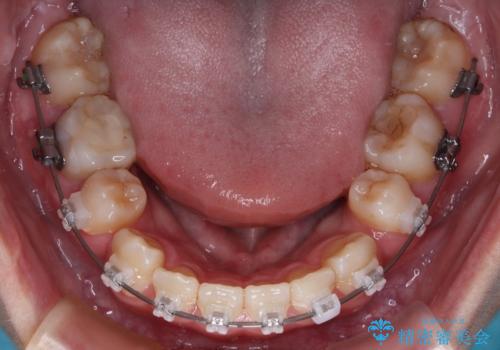

- 矯正装置

- クリアブラケット

- 治療計画

- 転勤により東京へ移られることになり転院先を探されていた患者様です。ワイヤー矯正の途中での急な転勤なうえ、今後2~3年以内に再度転勤になる可能性もあるというご事情でした。

そのため、限られた期間内に効率よく治療を完了するために、「抜歯スペースの確実な閉鎖」「深い噛み合わせ(過蓋咬合)の改善」の2点を主軸とした治療計画を立てました。